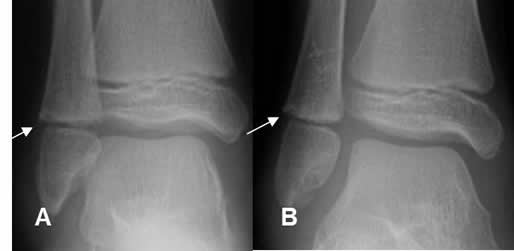

Fig 77. Salter tipo IV.

A: Rx AP y B: TAC reconstrucción sagital. Fracturas oblicuas con compromiso de las epífisis y metáfisis del tobillo y la rodilla.